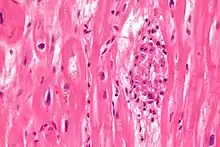

| Aschoff bodies are microscopic structures seen in patient with rheumatic fever | |

Microscopically, Aschoff bodies are areas of inflammation of the connective tissue of the heart, or focal interstitial inflammation. Fully developed Aschoff bodies are granulomatous structures consisting of fibrinoid change, lymphocytic infiltration, occasional plasma cells, and characteristically abnormal macrophages surrounding necrotic centres. Some of these macrophages may fuse to form multinucleated giant cells. Others may become Anitschkow cells or "caterpillar cells," so named because of the appearance of their chromatin.

The Aschoff nodules are foci of T lymphocytes, occasional plasma cells, and activated macrophages (Anitschkow cells) pathognomonic of rheumatic fever. These macrophages have abundant cytoplasm and central round nuclei in which chromatin condenses into a central, slender, wavy ribbon, the reason why they are sometimes called "caterpillar cells". They are especially found in the vicinity of small blood vessels in the myocardium and endocardium and occasionally in the pericardium, and also the adventitia of the proximal part of the aorta. Lesions similar to the Aschoff nodules may also be found in extra-cardiac tissues.